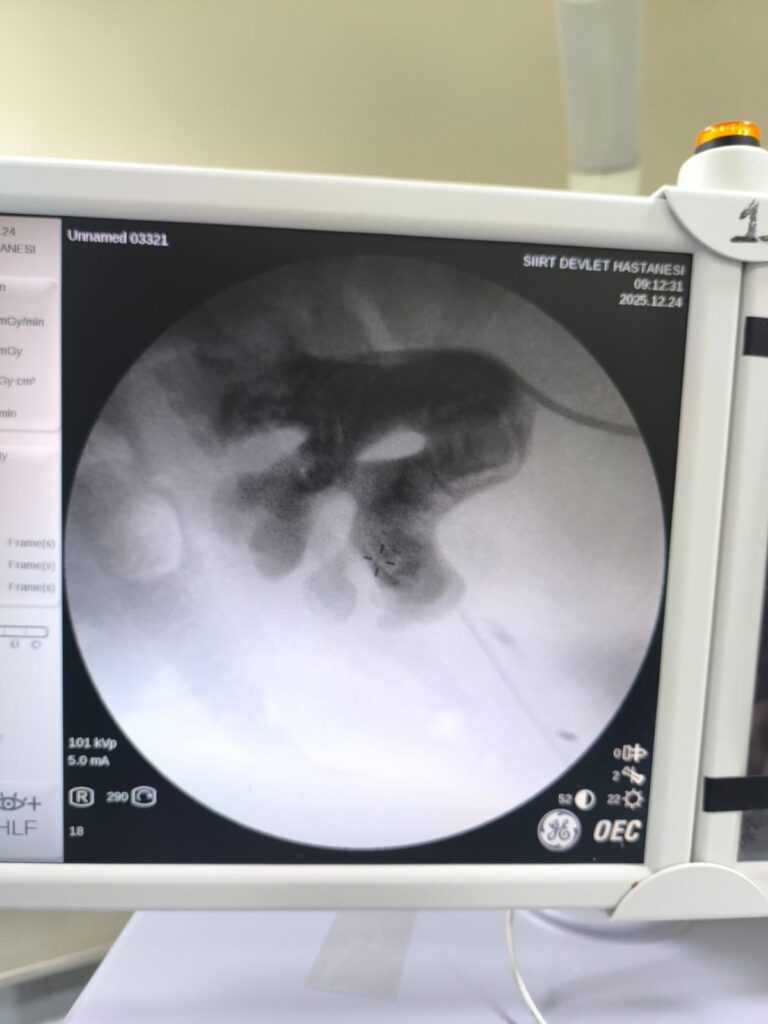

Yapılan değerlendirme sonucunda piyelonefrit (böbrek iltihabı) tanısı konuldu ve yatış yapılarak enfeksiyon tedavisi başarıyla tamamlandı. Tanı sürecinde yapılan Bilgisayarlı Tomografi (BT) görüntülemesinde böbreğin tamamını kaplayan, sert yapıda (950-1450 HU), literatürde staghorn olarak adlandırılan ve halk arasında “Geyik Boynuzu Taşı” diye bilinen büyük taş saptandı.

Staghorn taşlar böbreğin tüm boşluklarını doldurup, tekrarlayan enfeksiyonlara ve uzun vadede böbrek fonksiyon kaybına yol açabildiğinden tedavisi hayati önem taşımaktadır. Biz de bu vakamizda, Perkütan Nefrolitotomi (PCNL) yöntemiyle böbreğe küçük bir cilt kesisi üzerinden girerek endoskopik cihazlarla taşları parçalayıp çıkardık. PCNL, özellikle çapı 2 cm’den büyük ve kompleks taşlarda altın standart kabul edilmektedir. Normalde staghorn taşların temizlenmesi uzun süren ve çoğu zaman birden fazla seans gerektiren zorlu bir süreçtir.

Ancak ameliyat ekibimizin deneyimi ve hastanemizin modern altyapısı sayesinde, ciltten tek giriş yolu açılarak yaklaşık 1,5 saatlik bir seansta böbreğin tüm taş yükü başarıyla temizlendi. Ameliyat sonrası süreçte ise, hastamızın iyileşmesinde herhangi bir sorun yaşanmadı ve şifa ile taburculuğu planlandı. Siirt Eğitim ve Araştırma Hastanesi olarak hedefimiz, halkımıza en modern tedavi yöntemlerini sunmak ve bölgemizde sağlık hizmetlerinin gelişimine katkıda bulunmaktır. Son olarak, tedavi sürecinde desteğini esirgemeyen tüm ekip arkadaşlarımıza da ayrıca teşekkür ederim.”